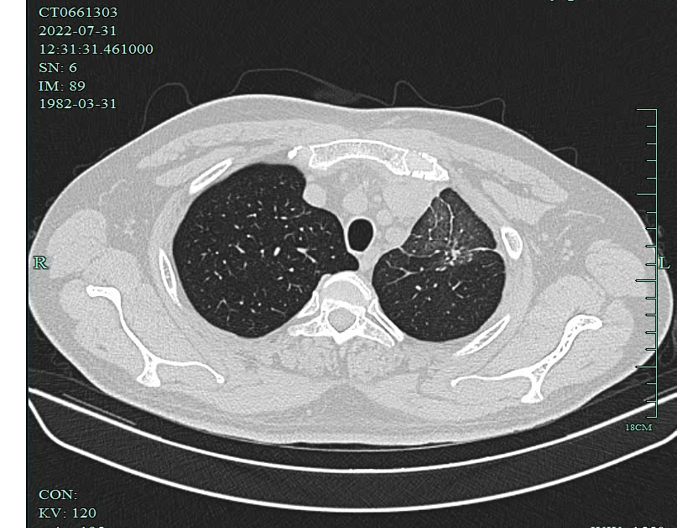

2022-07-31胸部CT:左上肺近纵隔肿块,大小 116X94mm,恶性肿瘤考虑,伴左肺上叶癌性淋巴管炎,纵隔内邻近多发血管受侵,与左心耳分界不清,纵隔淋巴结增大,心包积液。

影像学检查图像